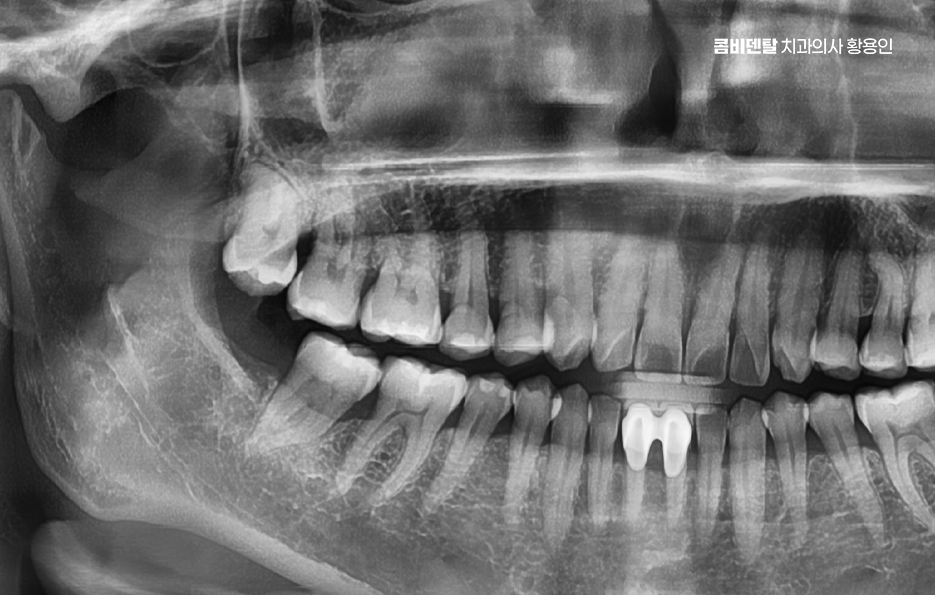

이런 경우에는 염증이 너무 심해지기 전에 빠르게 치과에 내원해서 사랑니 위치와 형태를 확인하는 X-ray 검사를 먼저 진행해야 하고 진단 결과 사랑니가 턱뼈에 수평으로 눌려 있거나, 인접 치아 뿌리를 밀고 있는 형태라면 단순히 약물치료만으로는 해결이 되지 않기 때문에, 염증을 가라앉히고 난 후 발치를 진행하는 방향으로 치료가 이루어지는 경우가 일반적이라 할 수 있어요

또 사랑니가 잇몸 안쪽에서 완전히 매복된 경우에도 사랑니 주변 잇몸 통증에 통증이 생기는 경우가 있는데 겉에서 보이지 않더라도 X-ray 상에서 보면 사랑니가 비스듬히 누워 있거나 옆 치아를 밀고 있는 경우가 많은데 이런 매복 사랑니는 염증이 없더라도 조용히 인접 치아의 뿌리를 괴사시키거나 인접면 충치를 유발하기도 해서 통증이 발생하지 않더라도 예방적 발치를 권유받는 경우도 있고 통증이 시작된 후에는 주변 뼈 흡수나 치주염, 잇몸 괴사로 진행될 가능성도 있기 때문에 사랑니 발치 판단을 적절히 세울 필요가 있어요